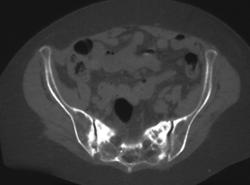

Diagnosis

Orbital Fracture